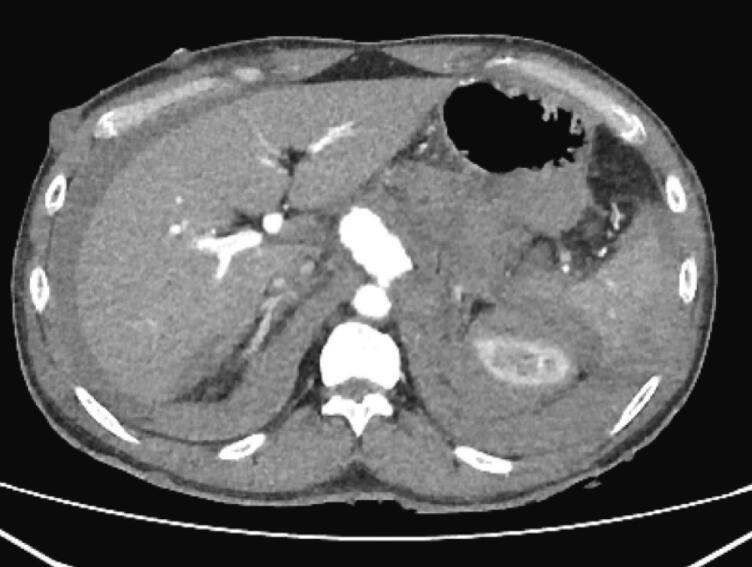

Fig. 2.

Axial view of CECT abdomen shows celiac artery aneurysm.

Contrast-enhanced CT abdomen revealed a celiac artery aneurysm without any active contrast leakage, but there was a retroperitoneal hematoma (Fig. 1 and Fig. 2).